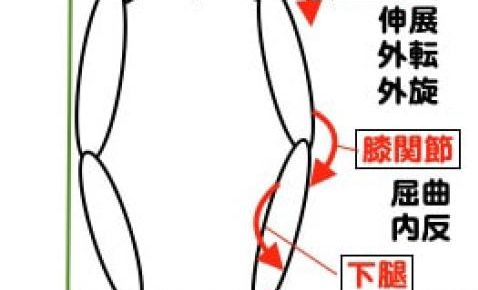

こんにちは!横浜本牧パーソナルトレーナー宮原崇です。 明日は節分ということで、父親の役割は決まって鬼役なのでコンディションを良くしていきたいと思います。 さて、昨日はもも裏の筋肉である大腿二頭筋が何しからの問題を起こすと…

こんばんは!横浜本牧パーソナルトレーナー宮原崇です。 確定申告を目前に大量なる資料整理に日々追われているので、時間という貴重な資源をどのように使うかが常に課題となっています。 さて、ひざの外側に痛みが発している時に、フィ…

こんにちは!横浜本牧パーソナルトレーナー宮原崇です。 今日は夏晴れでセミの鳴き声も心地よいです。 さて、午前のトレーニングセッションを終えてこれから午後の部となりますが、ひざ痛の方の多くが持っている身体の特徴をお伝えいた…